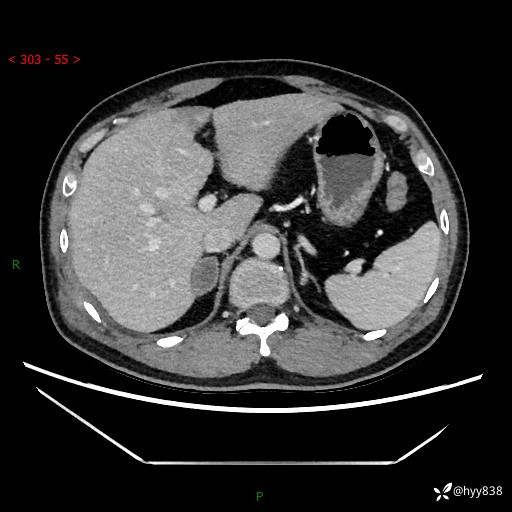

现病史:患者9月4日摔伤在深圳市宝安区中心医院行CT检查提示右侧肾上腺区结节(38*27mm),复查B超提示右侧肾上腺区可见一61*24mm异常低回声团,建议进一步检查。进一步完善增强CT后提示:右侧肾上腺区肿块及周围渗出改变,大致同前,考虑肾上腺腺瘤,不除外瘤内出血可能,否认阵发性头晕、头痛、出汗、乏力等不适,门诊以“ 右侧肾上腺肿瘤”收入住院。 起病来,患者精神、食欲、睡眠可,大便通畅,小便如上述,体力体重无明显改变。

肾上腺CT平扫

增强(动脉期+静脉期)